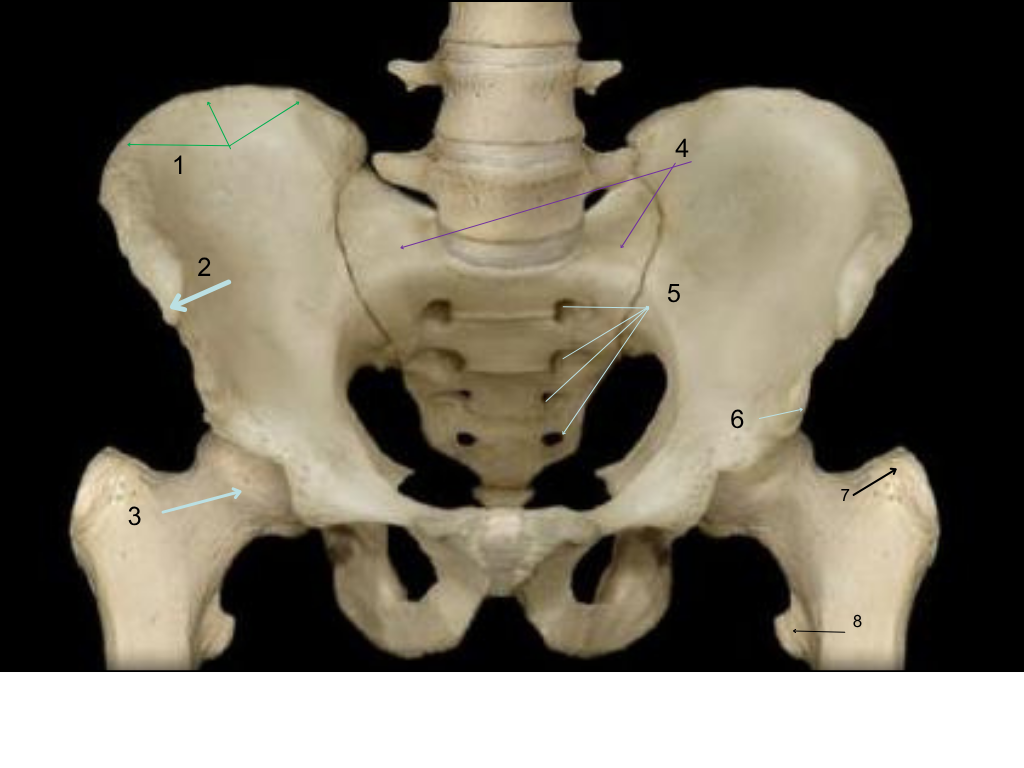

iliac crest

what is #1 pointing at?

ASIS (Anterior Superior Iliac Spine)

what is #2 pointing at?

femoral head

what is #3 pointing at?

sacral ala (wings)

what is #4 pointing at?

sacral foramina (openings or passages)

what is #5 pointing at?

AIIS (Anterior Inferior Iliac Spine)

what is #6 pointing at?